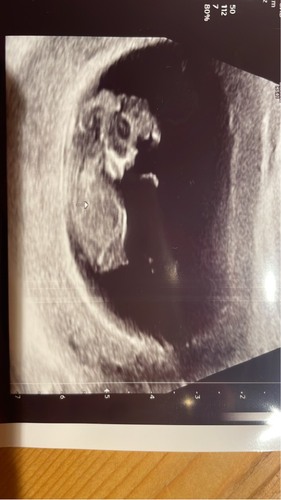

Iemand een idee? 13w 4 dagen 😳

Heb je nog meer foto’s? Volgens mij is de nub niet te zien op deze echo